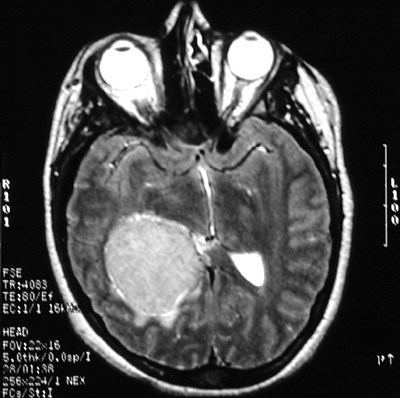

| The T1 weighted MRI scan in axial view above demonstrates another less common location for a meningioma, an intraventricular meningioma. In this location, a circumscribed mass could also be an ependymoma. Below can be seen the same right lateral ventricular mass with contrast enhancement in T2 weighted axial view and T1 weighted coronal view. |